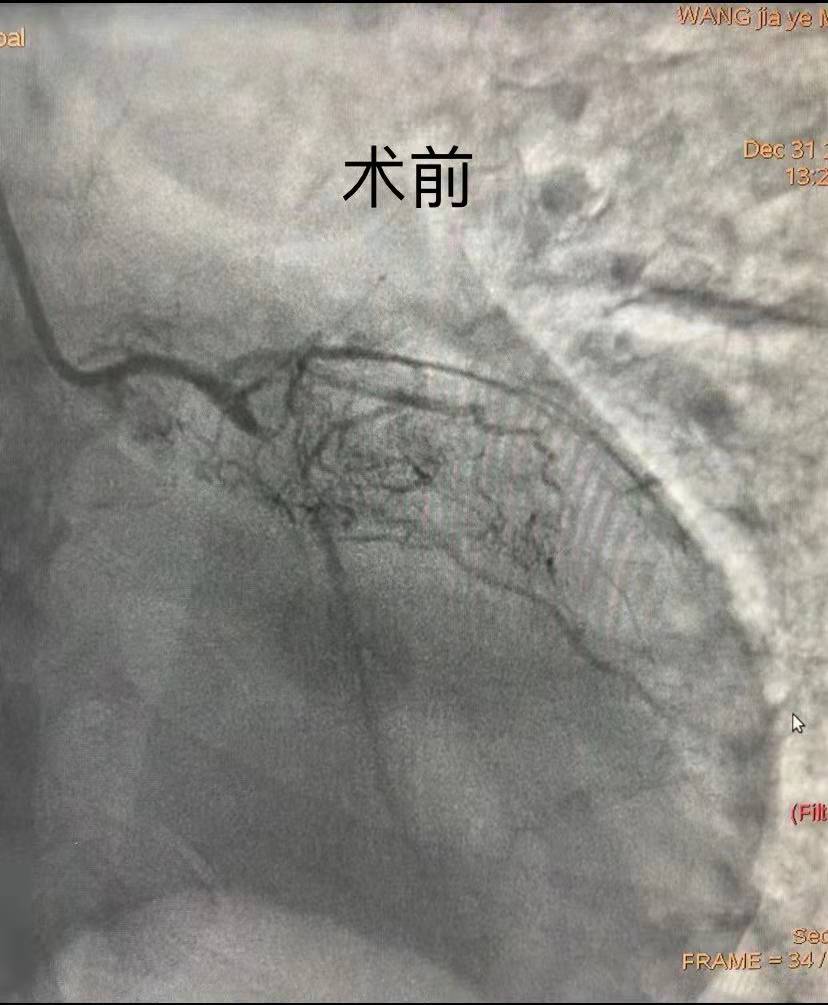

時(shí)間就是生命,時(shí)間就是心肌。在取得患者及家屬的理解及配合后,副院長(zhǎng)汪念東、副主任徐先進(jìn)及主任助理農(nóng)彥林帶領(lǐng)心血管內(nèi)科介入團(tuán)隊(duì)制定嚴(yán)密的救治方案及應(yīng)急預(yù)案,為患者施行緊急冠狀動(dòng)脈造影,證實(shí)多支血管彌漫性病變、LAD(冠狀動(dòng)脈前降支)慢性閉塞、LCX(冠狀動(dòng)脈左回旋支)近端次全閉塞、RCA(右冠狀動(dòng)脈)近端嚴(yán)重狹窄達(dá)90%。因患者血流動(dòng)力學(xué)極其不穩(wěn)定,用大劑量血管活性藥物維持基礎(chǔ)血壓的效果并不理想,團(tuán)隊(duì)為患者應(yīng)用IABP泵,完成術(shù)前生命支持系統(tǒng)。

團(tuán)隊(duì)綜合考慮后判斷,LCX是此次心肌梗死的“元兇”。開通病變部位的機(jī)會(huì)只有一次,必須做到“快、準(zhǔn)、狠”。汪院長(zhǎng)團(tuán)隊(duì)經(jīng)驗(yàn)豐富,技術(shù)嫻熟,導(dǎo)絲小心通過,球囊充分?jǐn)U張,最后在病變部位植入支架,所有操作一氣呵成。復(fù)查造影顯示,病變部位狹窄小于10%,手術(shù)獲得成功。